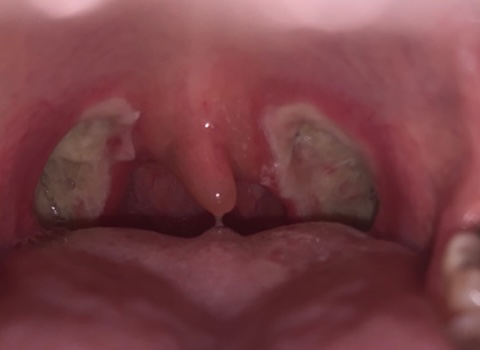

편도사진(혐오주의!)

혐오주의!!

수술 직후 수술 당일!

출혈이 있는 곳을 굽고 있어서 검게 보인다.진통제 때문인지 심하게 아프지는 않고 목 안에서 오징어 타는 냄새가 난다.얼음물에 식혀주면 조금 살 것 같은…